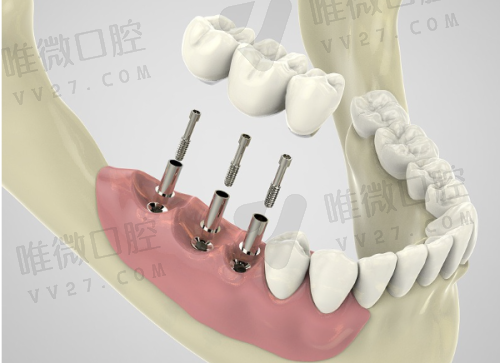

以当前2024年集采价为参考,目前单颗种植牙价格区间大致为3980元起至8980元起。根据不同品牌、牙体情况、种植方式(是否采用即刻种植、是否需要植骨等)费用略有差异。

- ITI种植系统:7980元起(瑞士进口)

- 韩国登腾等进口品牌:3980元起

举个例子,同样用ITI种植体,A同学年轻牙槽骨好,不需植骨,3980元起特别稳。B叔骨骼条件需要先植骨、做引导,再等愈合种牙,那可就得上7000-8000了。价格差异是对复杂程度的体现,不是“谁被坑了”。